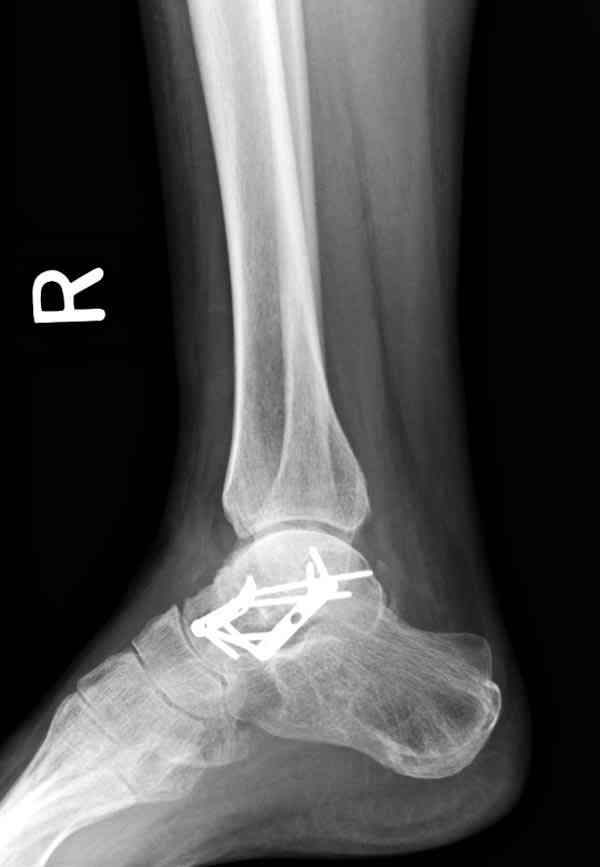

Случай с множественным оскольчатым переломом тарана оперированный из двойного доступа.

Через 2 мес.:

Через 8 мес.:

Через 14 мес.:

Для оценки состояния нужны дополнительные исследования, например

повторили рентгенограммы и доделали проекции, к единому мнению все еще не пришли

Решили не связываться с остеосинтезом, а сделать сразу берцово-пяточный блок. Снимки в приложении.

По завершении удлинения, наверно, заштифтуем.